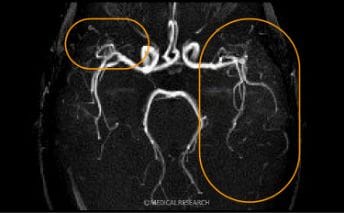

テスラの違い

【要確認】メディカルリサーチでは、3.0T(テスラ)の機器を用いてMRI撮影を行っています。

3.0T(テスラ)の機器で撮影すると末梢脳血管まではっきりと確認することができます。-

1.5T(テスラ)診断画像 -

3.0T(テスラ)診断画像